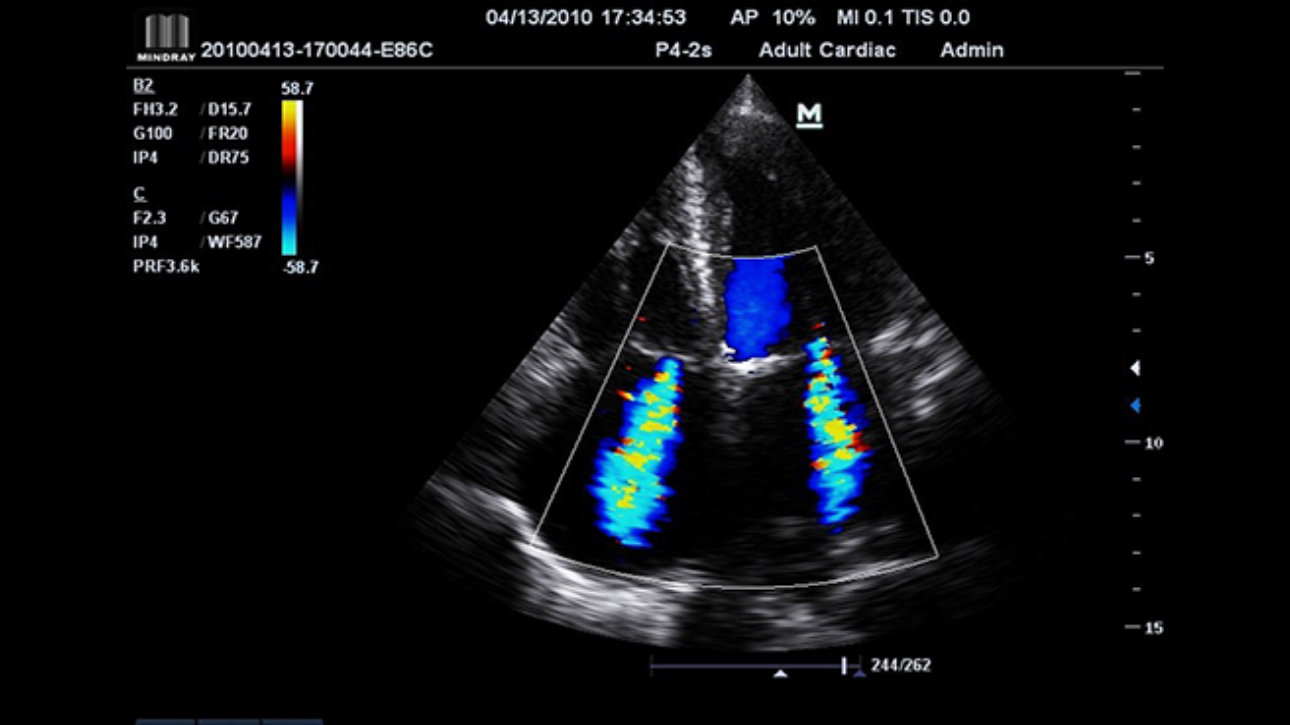

Award winning portable hand-carried color Doppler, M7 Premium is a High level system with excellent performance. Equipped with dedicated cardiac package and easy-to-use workflow software, M7 Premium offers an ideal packaged solution to address the needs of cardiologists.

Performance

PSHITM (Phase Shift Harmonic Imaging)

Purified Harmonic Imaging for better contrast resolution providing clearer images with excellent resolution and less noise.

iBeamTM(Spatial Compound Imaging)

Permits use of multiple scanned angles to form a single image, resulting in enhanced contrast resolution and improved visualization.

Tissue Doppler Imaging allows you to quantitatively evaluate local myocardial movement and function, providing complete TDI modes for faster and direct diagnoses.